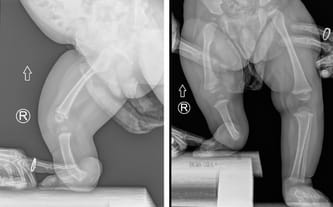

23 marca odbyliśmy konsultację z doktorem Paleyem w Paley European Institute w Warszawie. Podczas wizyty potwierdził, że wada Leosia jest bardzo trudnym i rzadkim przypadkiem, co wynika z połączenia dwóch poważnych schorzeń: hemimelii strzałkowej (czyli braku kości strzałkowej, skrócenie kończyny, deformacja stopy) oraz wrodzonego niedorozwoju kości udowej.

Zazwyczaj dzieci zmagają się tylko z jednym z nich, natomiast u Leona występują oba jednocześnie, co sprawia, że leczenie będzie długie i wieloetapowe. Bez operacji różnica w długości nóżek będzie się z czasem pogłębiać i w dorosłym życiu może sięgnąć nawet około 30 cm (!), co znacząco wpłynęłoby na jego sprawność i codzienne funkcjonowanie.

Podczas wizyty wykonano nowe zdjęcia RTG. Na ten moment różnica długości nóżek wynosi już 9,5 cm… To pokazuje, jak dynamicznie postępuje wada i jak pilnie Leon potrzebuje specjalistycznego leczenia.

Leoś urodził się ze znacznie krótszą prawą nóżką. Lekarze przewidują, że różnica długości może osiągnąć nawet 30 centymetrów. Skrócona kość udowa, skrócona kość piszczelowa, brak kości strzałkowej, zdeformowana stopa z trzema złączonymi paluszkami… Diagnoza: hemimelia strzałkowa – wada, która zabiera beztroskie dzieciństwo i odbiera szansę na normalny krok.